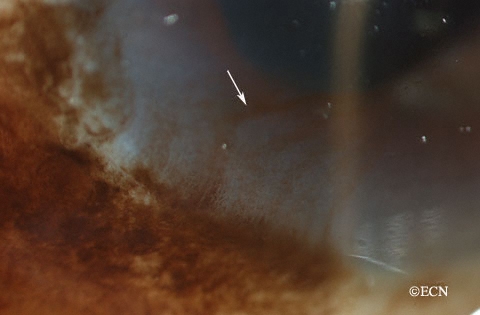

PAM은 중년층에서 발생하는 황갈색 반점이 전형적입니다.

편평하고 윤곽이 분명하지 않은 황갈색 혹은 흑갈생 색소침착이 나타납니다.

햇빛 노출이 많은 윤부에서 주로 많이 발생하기에

이측 및 하측의 사분면의 안구 결막에서 호발합니다.

보통은 편평한 병변으로 시작되는데, 불규칙한 색소 침착을 보입니다.

병벼이 편평하지 않고 융기되어 나타나는 경우에는 악성 흑색종을 의심해야합니다.